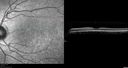

12 year old female She went last December for her regular checkup and spots were noted on the retina in the periphery. Her vision is fine and there is no family history of retinal disease. She has difficulty seeing at night and finding her way in a dark theater. VA OD: Dcc20/20-1 NccJ1+ VA OS: Dcc20/20 NccJ1+

Fundus Albipunctatusvista 962 veces12 year old female with normal vision. She has 4 siblings all of whom have either white spots or spots on IR. Genetic testing by parents was deferred.00000